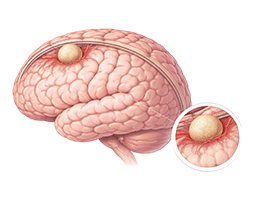

뇌수막종 (Meningioma)

뇌동맥류 (Cerebral aneurysm)